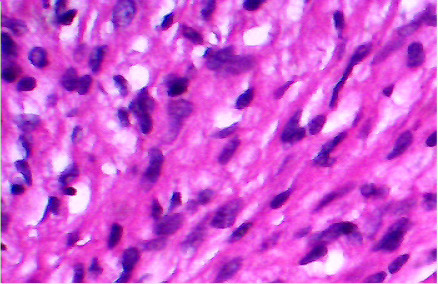

Background: Cellular schwannoma is a benign variant of classic schwannomas. It is an extremely rare condition to be derived from nasal septum.

Case presentation: a cellular schwannoma of the nasal septum is described in a 10-year-old Sudanese girl presented with nasal obstruction. The tumor was treated surgically by a trans-nasal approach. Pathological examination of the resected tumor showed cellular schwannoma. The tumor cells were immunoreactive for S-100 protein. The patient has been doing well for 10 months with no evidence of tumor recurrence.